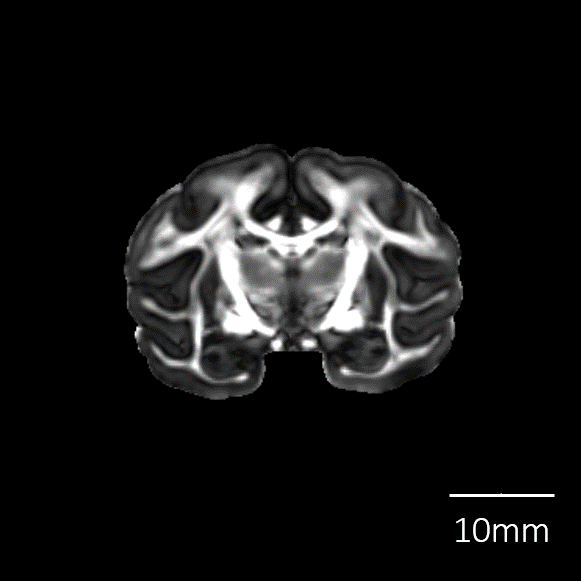

脳標本画像

|

脳表再構成画像 |

![]() |

| T2強調画像 |

| 拡散強調画像 |